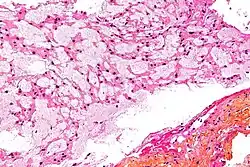

Anatomía patológica

Los cordomas son tumores de lento crecimiento, con una duración de los síntomas antes del diagnóstico de más de cinco años. Aproximadamente un 50% se localizan en la zona sacrococcígea, 35% en el área esfeno-occipital del cráneo y el resto a lo largo de la columna vertebral. Los tumores sacrococcígeos son más frecuentes en la quinta y sexta décadas de la vida, mientras que muchos de los esfeno-occipitales ocurren en niños y adolescentes. En los primeros, una porción del sacro es destruida por una reacción osteolítica, o más raramente, por una proceso osteoblástico. El espacio retroperitoneal es frecuentemente invadido por extensión directa. El tumor puede crecer lo suficiente como para obstruir la luz del intestino grueso, incidir sobre la vejiga o infiltrar la piel por extensión directa. Los cordomas esfeno-occipitales pueden presentarse como masas nasales, paranasales o nasofaríngeas, como afectación múltiple de nervios craneales o con destrucción ósea. Excepcionalmente, pueden causar hemorragia aguda pontocerebelar fatal.[6]

Macroscópicamente, se trata de una masa gelatinosa y blanda que contiene áreas de hemorragia.

Microscópicamente, recuerda al tejido notocordal normal en sus distintos estadios de desarrollo. Crece en cordones celulares y lóbulos de células separados por una cantidad variable de tejido mucoide intercelular. Algunas de las células neoplásicas (conocidas como fisalíferas) son extremadamente grandes, con citoplasmas vacuolados y núcleos vesiculares prominentes. Algunas de las vacuolas citoplásmicas contienen glucógeno. Otras células tumorales son pequeñas, con núcleos inaparentes y sin nucléolos visibles. Generalmente hay pocas mitosis, o estas ausentes. Puede haber áreas de cartílago o hueso. Hay tres variantes histopatológicas del cordoma: clásica o convencional (la descrita), condroide y desdiferenciada.[7]